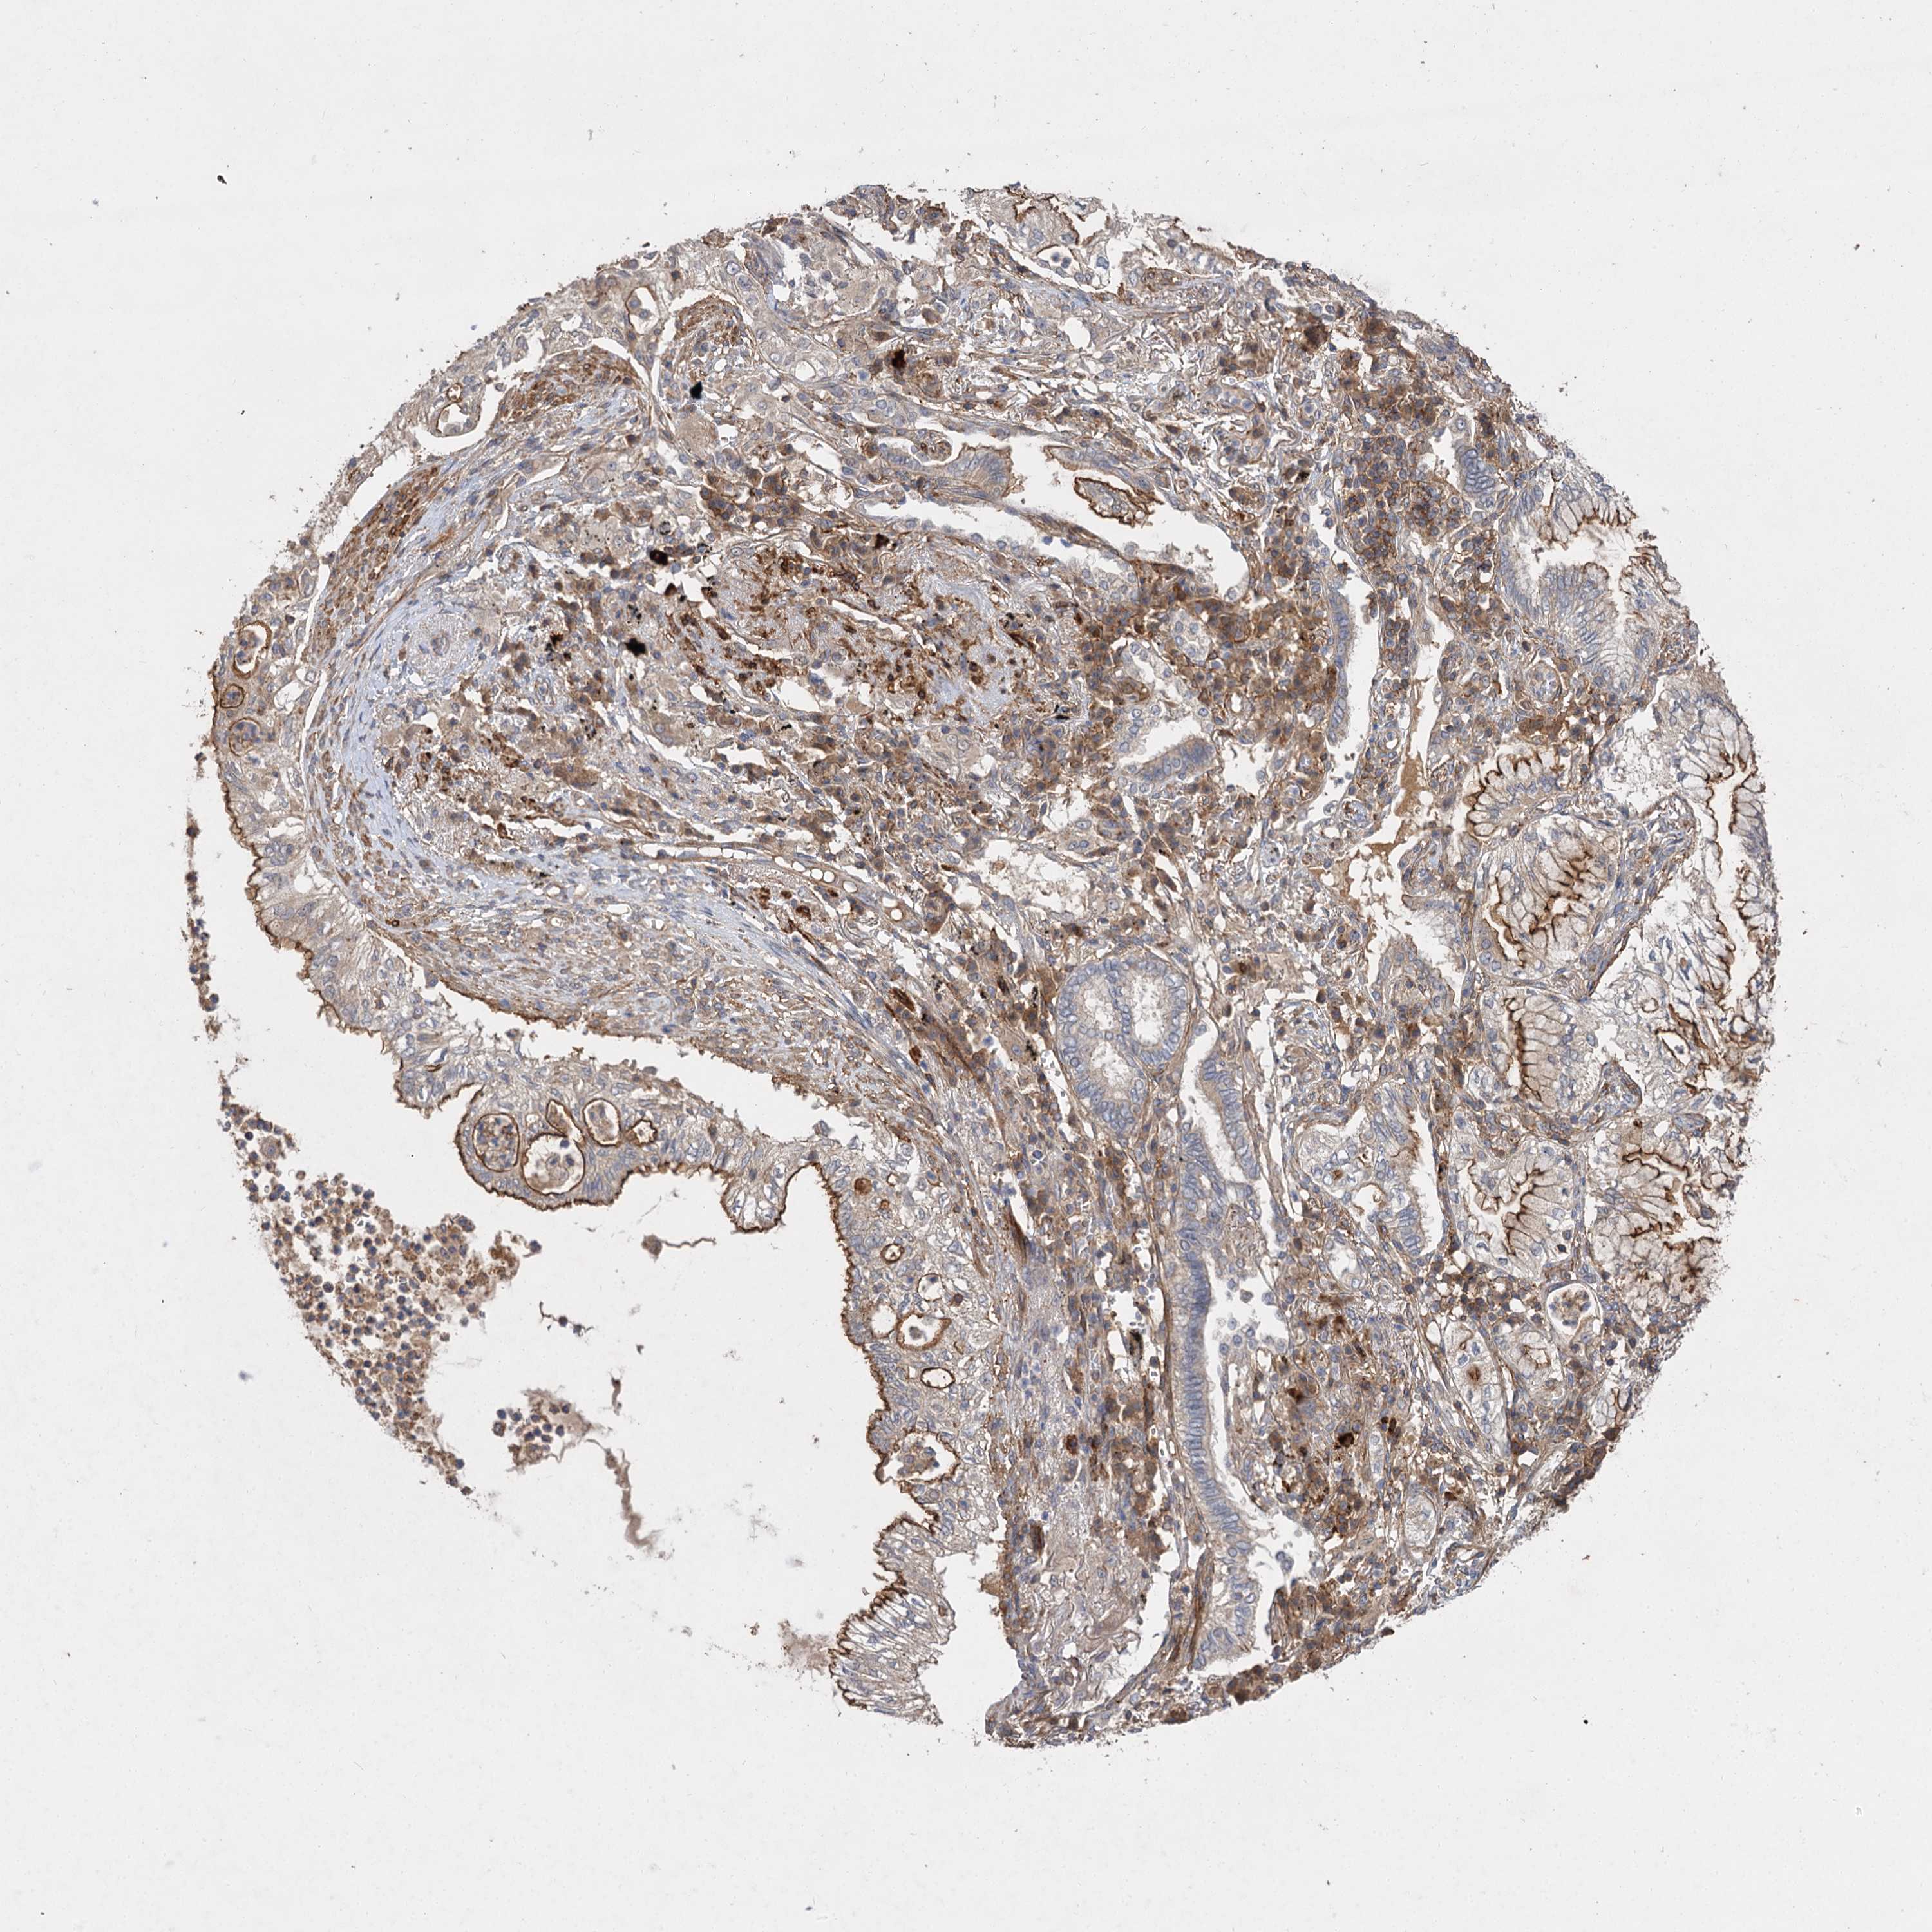

TCGA RNA samplesi

RNA-seq data is reported as average FPKM (number Fragments Per Kilobase of exon per Million reads), generated by the The Cancer Genome Atlas (TCGA) .

Normal distribution across the dataset is visualized with box plots, shown as median and 25th and 75th percentiles. Points are displayed as outliers if they are above or below 1.5 times the interquartile range. FPKM values of the individual samples are presented next to the box plot.

Average pTPM 7.3

Number of samples 489